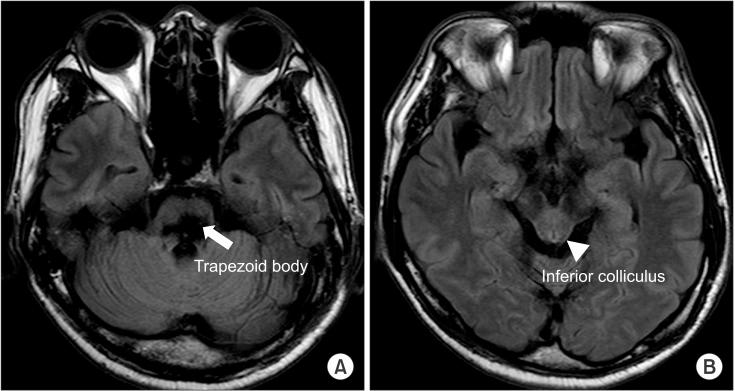

A pontine intracranial hemorrhage (ICH) evokes several neurological symptoms, due to the various nuclei and nerve fibers; however, hearing loss from a pontine ICH is rare. We have experienced a non-traumatic pontine ICH patient, with hearing loss. A 43-year-old male patient had a massive pontine hemorrhage; his brain magnetic resonance imaging revealed the hemorrhage on the bilateral dorsal pons, with the involvement of the trapezoid body. Also, profound hearing loss on the pure-tone audiogram and abnormal brainstem auditory evoked potential were noticed. Fifty-two months of long-term follow-up did not reveal any definite improvement on the patient's hearing ability.

桥脑出血(ICH)由于各种神经核团和神经纤维会引发多种神经症状;然而,桥脑出血导致的听力丧失较为罕见。我们遇到过一名非创伤性桥脑出血患者伴有听力丧失。一名43岁男性患者发生了大量桥脑出血;他的脑部磁共振成像显示双侧脑桥背侧出血,累及梯形体。此外,纯音听力图显示重度听力丧失,脑干听觉诱发电位异常。52个月的长期随访未发现该患者听力能力有任何明显改善。